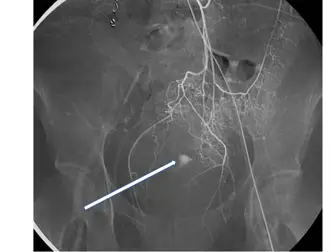

長期洗腎病患突然解血便,在急診室曾發生休克,緊急血管攝影檢查(下腸繫膜動脈, inferior mesenteric artery),如圖,箭號所指之腸出血最可能源自下列那一條血管?

本題圖片為血管攝影(digital subtraction angiography, DSA),為下腸繫膜動脈(IMA)注射顯影劑後的影像:

- 左側可見主動脈(aorta)的一個分支向下走行入骨盆腔

- 白色箭號指向骨盆腔左側的一條血管,可見局部顯影劑染色/出血灶(extravasation)或異常聚積

- 該血管走行路徑從腹部下行進入骨盆腔,越過左髂動脈前方後向下進入直腸旁

- 分支分布範圍對應**直腸上段(upper rectum)**的供血區域

根據 IMA 的解剖:IMA 分為三個主要分支:左結腸動脈(left colic artery)、乙狀結腸動脈(sigmoid arteries)及上直腸動脈(superior rectal artery, SRA)。其中上直腸動脈為 IMA 的終支(terminal branch),下行入骨盆腔供應直腸上段,走行路徑與影像中箭